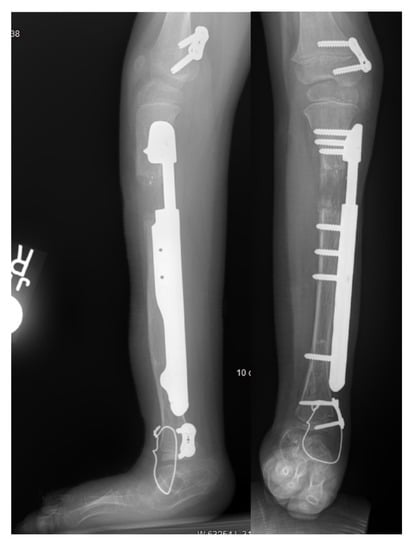

With the recent advancement of internal lengthening devices, there is a trend to perform lengthenings internally if possible. External fixators still play an important role in tibia lengthening, especially in young children where physeal and bone diameter or length prevent insertion of a rigid nail. All-internal lengthening, with an extramedullary implant position is an emerging option in patients who would traditionally require an external fixator for lengthening in the femur and tibia. Extramedullary implantable limb lengthening (EMILL) is a new technique, first performed by the senior author in 2015 [32], that uses an implantable nail attached to the bone like an internal-external fixator. EMILL has been shown to be a safe technique to lengthen the femur or tibia in patients in which an external fixator would otherwise be necessary [32,33,34]. There were 4 patients who underwent EMILL for tibial lengthening reported by Shannon et al. [34]. None had axial deviation. One had a locking screw breakage and one had a screw head erode through the thin skin on the medial side of the leg. Although there were no reported axial deviations, the authors have subsequently had cases of axial deviation with tibial EMILL (Figure 7). The senior author, in collaboration with Nuvasive Specialized Orthopedics has continued the evolution of the Precice mechanism to develop an implantable limb lengthening plate called the Precice plate. The Precice plate device was specifically designed for EMILL and has now was cleared by the FDA in December of 2019 (Figure 9). It has been used by the authors in 20 cases and will be the subject of a future report. A lengthening plate further expands the indications for EMILL and the ability to utilize implantable lengthening for younger children [35].

Figure 9.

AP and lateral radiographs of a 4-year-old girl who had a previous SUPERankle procedure and one 5 cm lengthening with an external fixator. She had a Precice plate applied to the medial side of the tibia. To prevent equinus the foot was tethered anteriorly with a temporary arthrodesis wire. The Precice plate (Nuvasive Specialized Orthopedics, Aliso Viejo, CA, USA) can lengthen up to 4.5 cm.